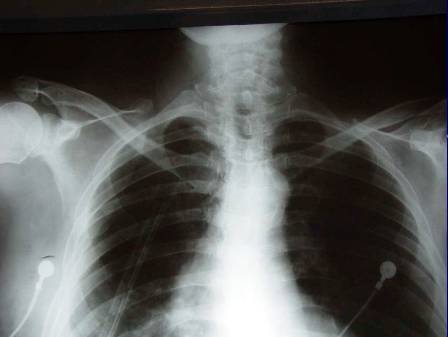

1.Generalizace (pac.L.U. . ––RTG, CT)

Generalizace (pac.L.U. . ––RTG, CT)